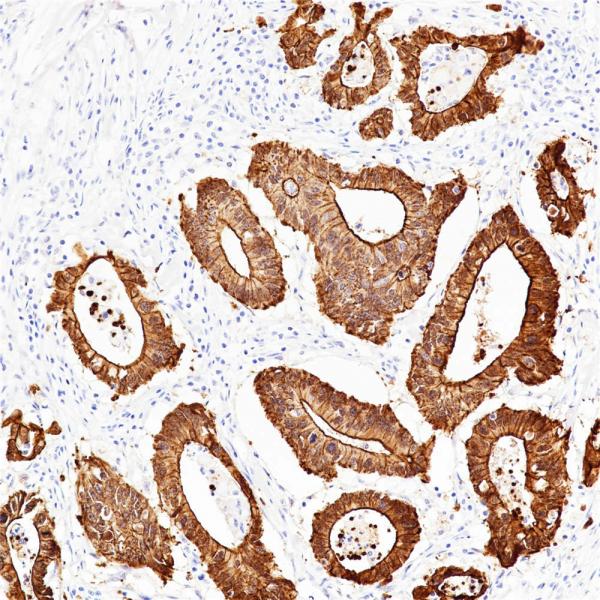

Von Willebrand Factor (VWF)

BP6084